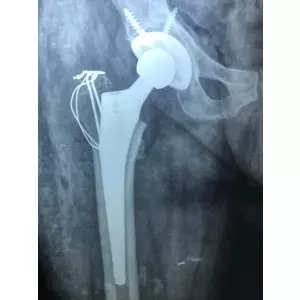

Dr Samir Nanavati